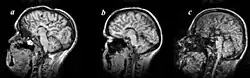

Agenezja ciała modzelowatego (łac. agenesis corporis callosi, ang. agenesis of corpus callosum, ACC) – wada wrodzona przodomózgowia, polegająca na różnego stopnia niedorozwoju spoidła wielkiego mózgu (ciała modzelowatego). Wada ta wykazuje dużą różnorodność, od zwykłego braku tej struktury mózgu po częściowy brak (zachowanie przedniej części przy braku tylnej).

Wadę rozpoznaje się metodami obrazowania mózgu (TK, MRI). Widać wtedy poszerzenie światła komór bocznych mózgu (obraz motyla z rozłożonymi skrzydłami). W miejscu ubytku mogą rozwijać się tłuszczaki (lipomata). W większości przypadków zachowane są podłużne pęczki spoidła, tzw. pęczki Probsta (Probst bundles), nieobecne są też zakręt obręczy i niekiedy sklepienie oraz spoidło przednie.